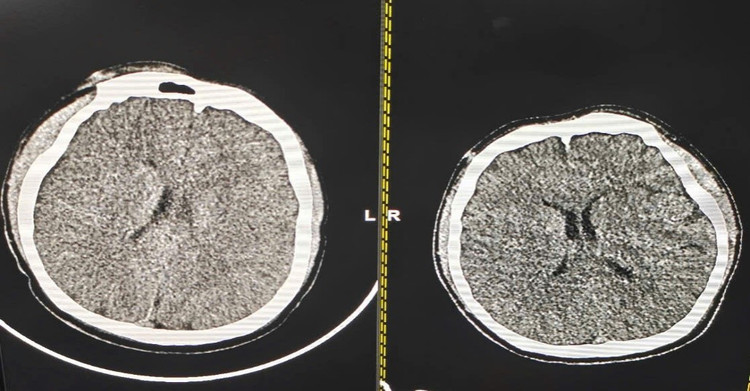

| Hình ảnh phim chụp cắt lớp vi tính sọ não của bệnh nhân tại thời điểm nhập viện và sau 5 ngày điều trị tại Khoa Hồi sức nội khoa và chống độc - Ảnh BVCC |

Tại Khoa Hồi sức nội khoa và chống độc, bệnh nhân được thông khí cơ học, kiểm soát thân nhiệt chỉ huy, chống động kinh, phù não. Sau 5 ngày điều trị, bệnh nhân dần hồi phục ý thức, được rút ống nội khí quản vào ngày thứ 6 và ra viện vào ngày thứ 10 trong tình trạng tỉnh táo, không để lại di chứng thần kinh.